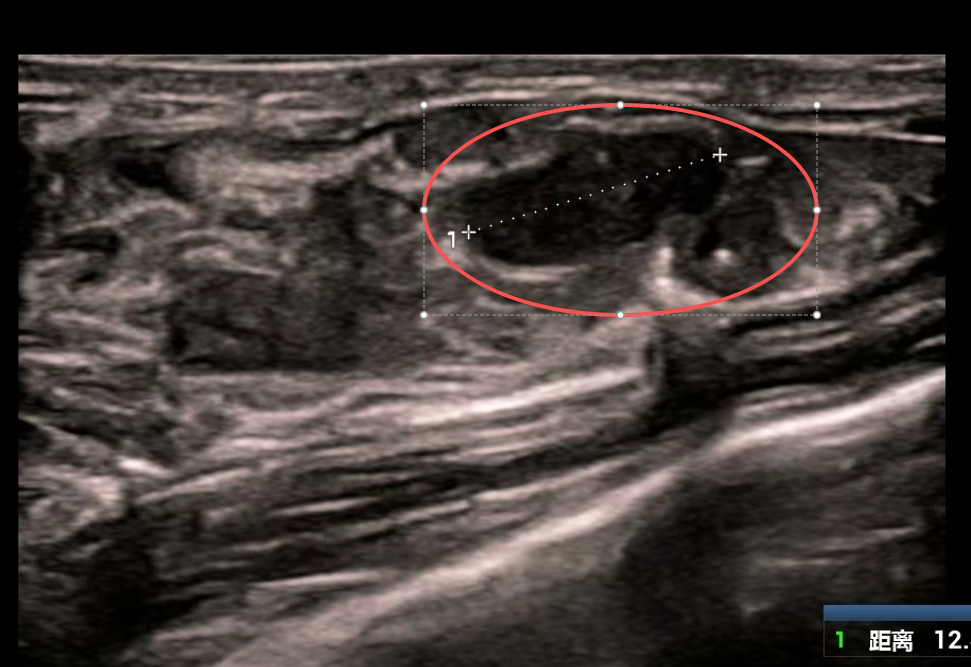

美美的检查结果让医生与家属心头一紧:她的双侧乳房内竟散落84个大小不一的肿块,其中最大一个达6厘米×5厘米,如同鹅蛋大小。

虽然彩超乳腺分级标准为3级,穿刺活检显示为良性结节,但如此庞大的数量和体积的肿块,已严重威胁乳腺健康,需手术处理。

面对84个肿块这一罕见情况,医生迅速启动多学科会诊,为美美制定个体化手术方案以兼顾清除效果与乳腺保护,经手术精准切除72个较大肿块;剩余12个小结节,在术中超声引导下,行乳房肿物低温等离子体消融术。